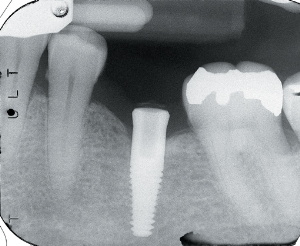

Figure 4. Soft tissue circular trephine used to create surgical and implant placement channel.. Figure 5. Implant in place with healing cap in place. Figure 6. Radiograph of the implant at progressive osseointegration evaluation appointment.

At 2 months the patient returned for a quick, 5-minute examination. A periapical radiograph was obtained to verify an intimate bone-to-implant surface contact. The implant was also examined physically and visually for mobility, pain, and signs of infection. If the examination demonstrates a lack of mobility, pain, and/or infection, and demonstrates intimate bone-to-implant contact, progressive osseointegration; is established, paving the way for prosthetic delivery (Figure 6).